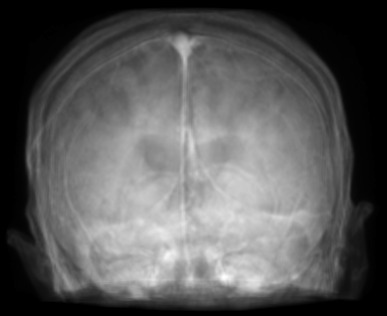

Figure 2: Inputs and outputs of the guided filtering pipeline based on the WDSR network. T1 & T2 MRI pairs (a)-(e) and CT & MRI projection images (f)-(j).

In Fig. 2 and 4, exemplary input, output and label images of the pipeline are presented for both tasks. Additional super-resolved images for both network architectures with and without the guided filter can be seen in Fig. 3. The results show a consistently high quality over both, the tomographic and the projective domain, as well as both tasks. Corresponding quantitative evaluation can be found in Table I and II. For SR, the WDSR network, i.e., the designated super resolution network, performs consistently better for both datasets with and without the guided filter. Applied to the tomographic images, the approaches without the guided filter deliver slightly better quantitative results. For the projection images this difference diminishes and both approaches are on par. In the case of denoising, the approaches with the guided filter deliver a lower mean absolute error while the structural similarity is increased without it. Though, the measurable differences are only marginal. The results generated by the plain guided filter without the learned guidance map are numerically worse than the approaches empowered by the guidance map generator for all tasks. This observation is most prevalent when observing the results of the tomographic T1 and T2 Flair images for SR, while for denoising the results are closer to the deep learning-based approaches.

In general, the decrease in image quality metrics w.r.t. to smaller radii is much stronger for the tomographic T1 and T2 Flair images than for the projection images. We assume the reason for this to be the difference in resolution of both datasets. The projection images resemble the ground truth more closely from the outset when compared to the tomographic images as seen in Fig. 2(b) and 2(g), respectively. Consequently, more information has to be generated by the networks. As the guided filter is sensitive towards correlation between the input and guidance map the constraints on the applicable changes are more severe.